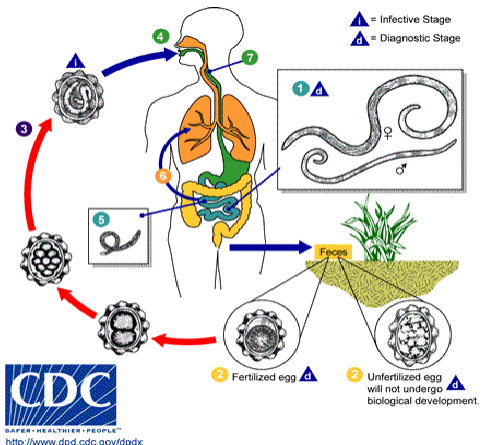

life cycle of ascaris lumbricoides

feces with ascaris eggs exposed to environment

unfertilized eggs will not undergo development into adult worm

fertile egg goes through multiple developmental stages

eventually becomes an embryonated egg w L3 larvae (infectious form)

definitive host ingests embryonated eggs

larvae coughed up and swallowed & maturation continues in small intestine

adults inhabit small intestine

key info about ascaris lumbricoides life cycle

Eggs immature when passed

Mature in environment

Ingested, hatch in gut

Larvae migrate to lungs

Coughed up and swallowed

Mature into adults in gut

unfertilized ascaris eggs

90 x 40 um

Oval, yellow brown stained

Thick shell, may be corticated (albuminous coating)

Undifferentiated internal material

If only see these, the host is only infected with FEMALE worms

fertile ascaris eggs

45 x 60 um

Yellow brown

Thick transparent shell

May have cortication

Cleavage of internal yolk will be seen; sometimes formed larvae seen inside eggs

answer the following about a lumbricoides:

What form is shed/acquired from the human?

If, an egg, is it embryonated or not?

If it is a larvae, what kind of larvae?

What hatches from the egg?

can shed both unembryonated/embryonated eggs in feces

infective larvae hatches from the egg (happens in the human)

answer the following abt a lumbricoides:

intermediate host? reservoir host?

What is the infective stage that gets back into the human?

How does the infective stage get back into the human?

General info about what happens once it gets back into the human.

Where do adults live?

no intermediate/reservoir host—completes its life cycle in humans

infective stage: fertilized ascaris egg embryonated w L3 larva

humans ingest fertilized egg

egg hatches & matures into an adult worm in the small intestine

adults live in the small intestine